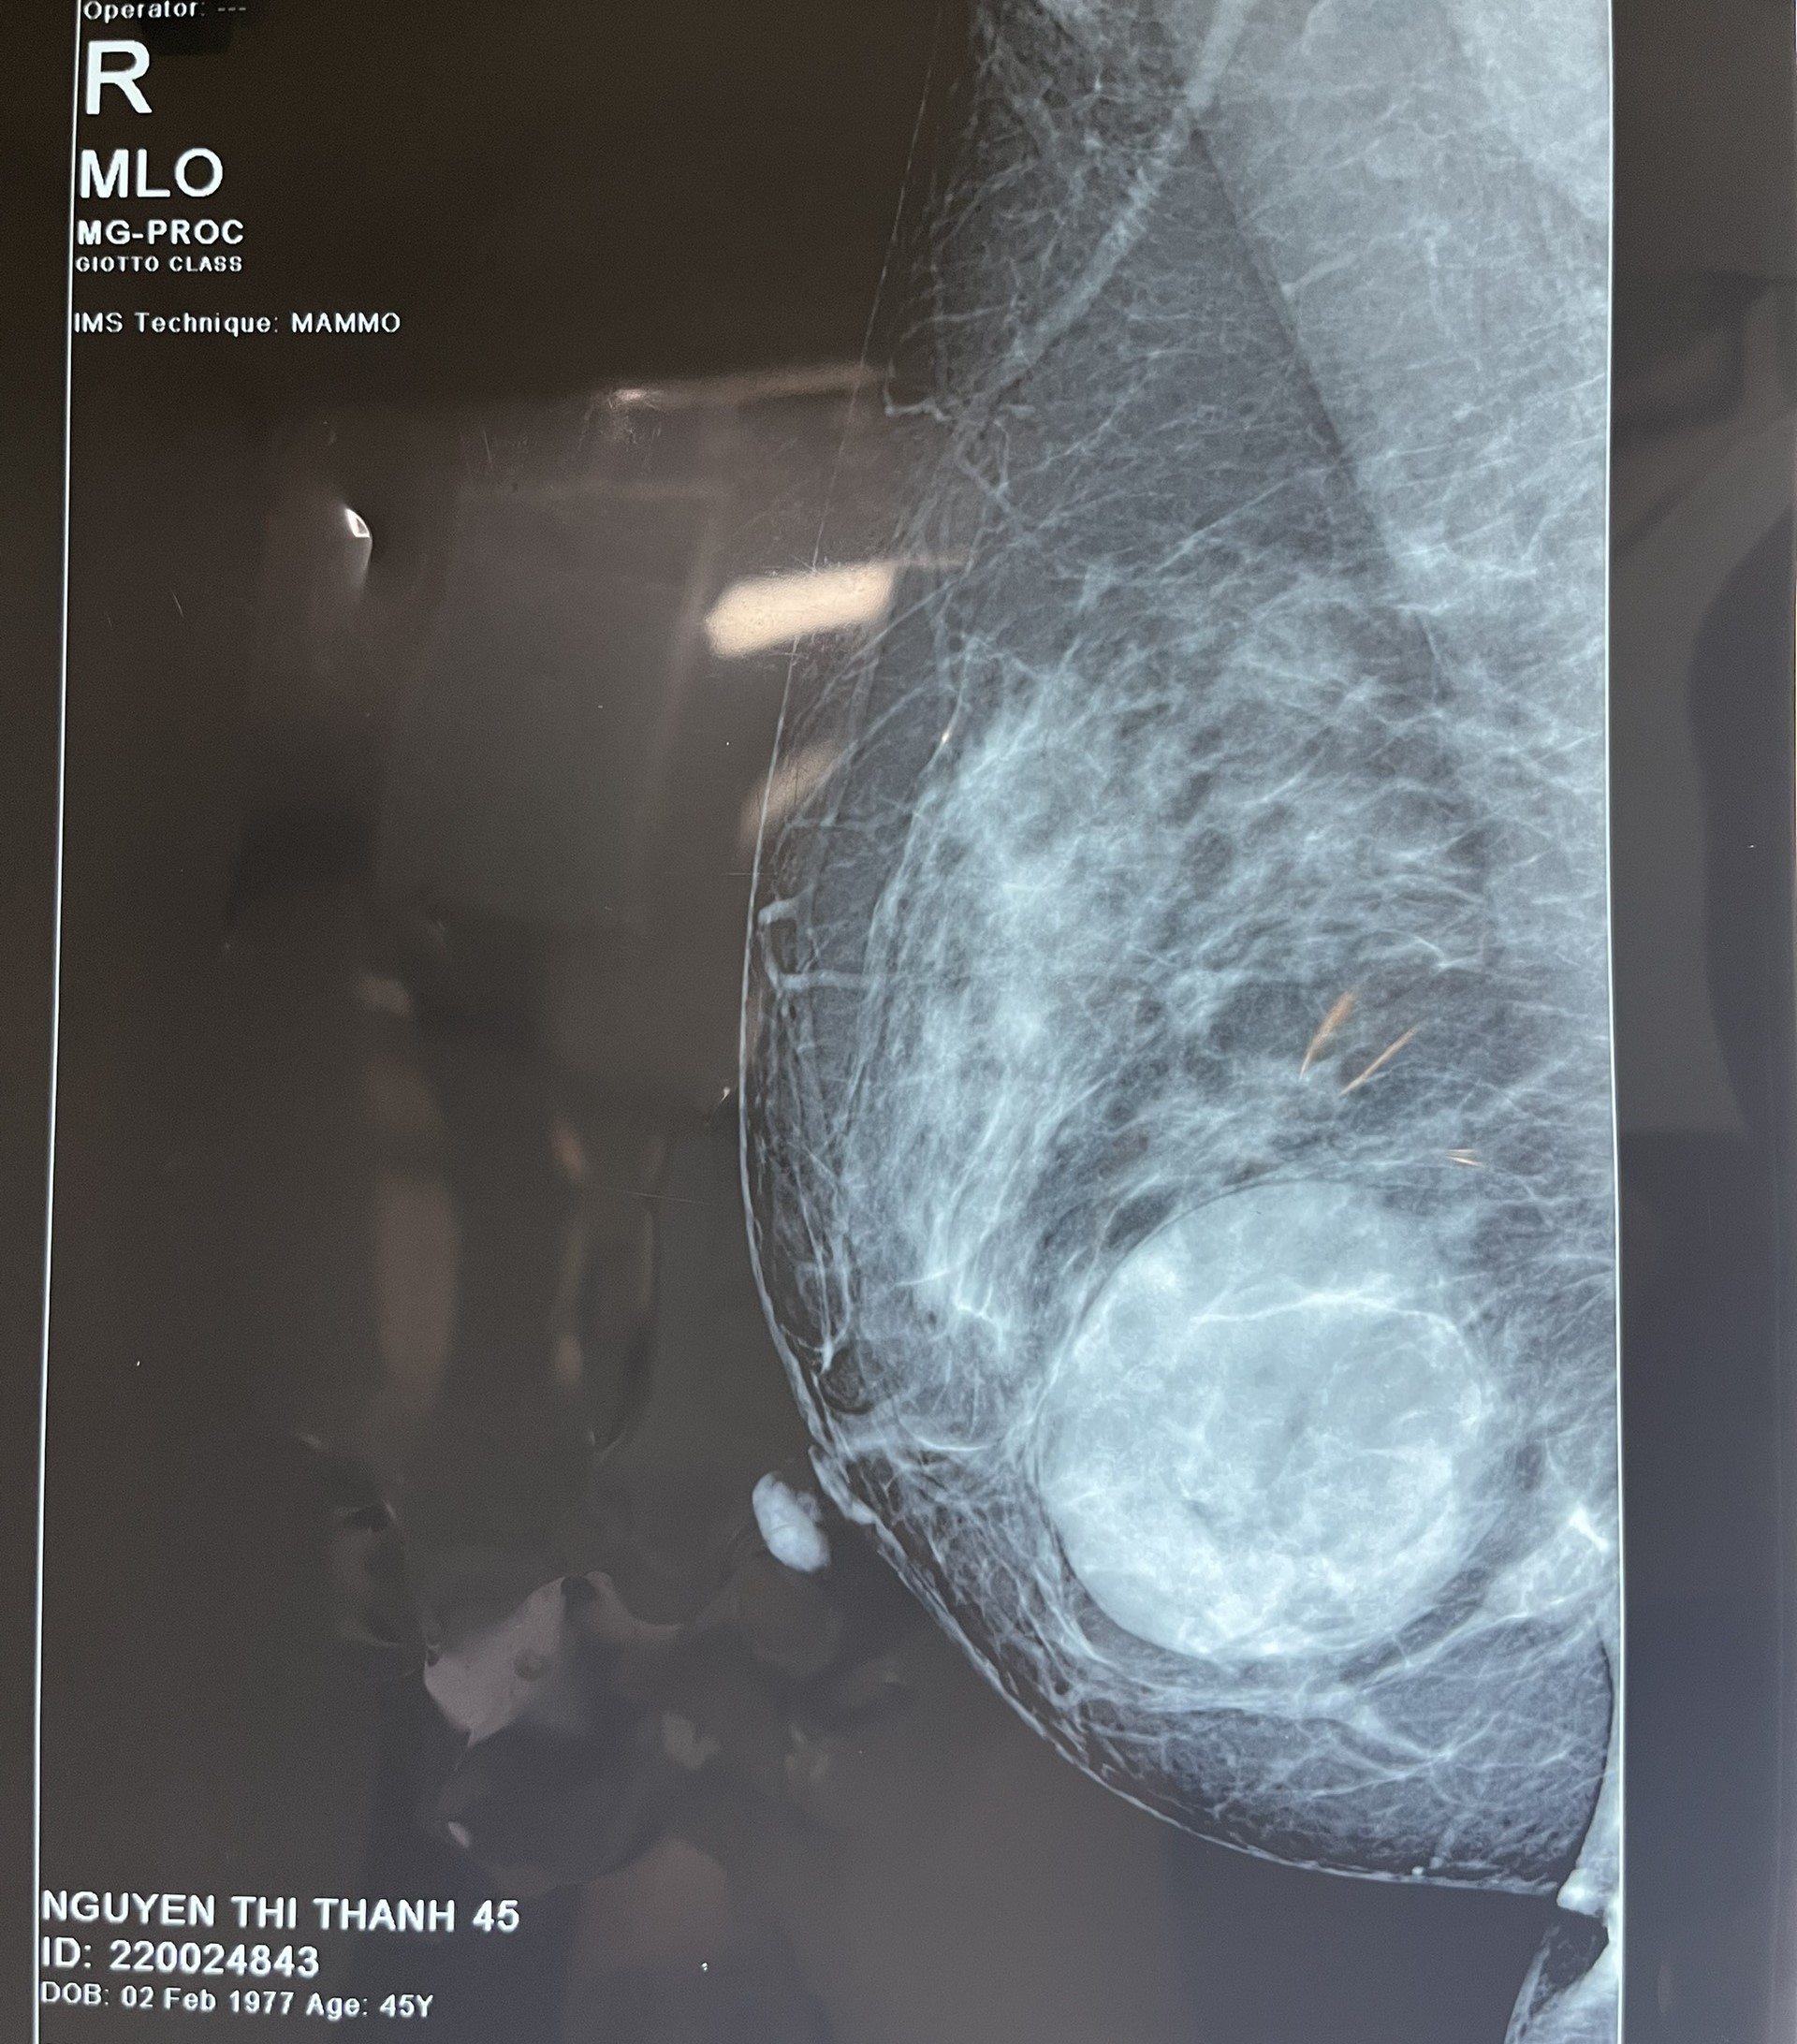

Chị N.T.T 45 tuổi, ở xã Phúc Khánh huyện Yên Lập mỗi lần đến kỳ kinh nguyệt đều cảm thấy vùng ngực căng tức, chị sờ nắn thì phát hiện ra mình có khối khu trú tại vú đã 1 năm nay. Chị T đã đi thăm khám tại rất nhiều cơ sở y tế trong và ngoài tỉnh và đều được chẩn đoán là u xơ tuyến vú, cần phẫu thuật cắt u. Ngày 22/9, chị đến TTYT huyện Yên Lập để khám lại và quyết định lựa chọn phương pháp phẫu thuật cắt bỏ khối u ra khỏi cơ thể. Kết quả khám và siêu âm cho thấy tuyến vú bên phải của người bệnh có nốt âm vang hỗn hợp kích thước lớn 4x5cm. Với sự hỗ trợ chuyên môn từ chuyên gia hàng đầu của Bệnh viện đa khoa tỉnh Phú Thọ, kíp phẫu thuật, gây mê hồi sức TTYT huyện Yên Lập tiến hành hội chẩn và thực hiện phẫu thuật cắt u vú cho người bệnh.

Trước phẫu thuật, người bệnh được thực hiện các cận lâm sàng đảm bảo an toàn cho cuộc phẫu thuật như siêu âm tim, điện tim, định nhóm máu, xét nghiệm máu chảy, máu đông,… Bắt đầu phẫu thuật, người bệnh được gây mê nội khí quản, các bác sỹ tiến thành sát khuẩn vùng vú phải. Với đường rạch dài 3cm, u phần mềm tuyến vú nặng 250 gram có bờ đều, ranh giới rõ đã được bóc ra. Sau gần 2h đồng hồ, ca phẫu thuật đã thành công, người bệnh tỉnh táo và đã được trở về phòng bệnh nghỉ dưỡng, điều trị hậu phẫu.